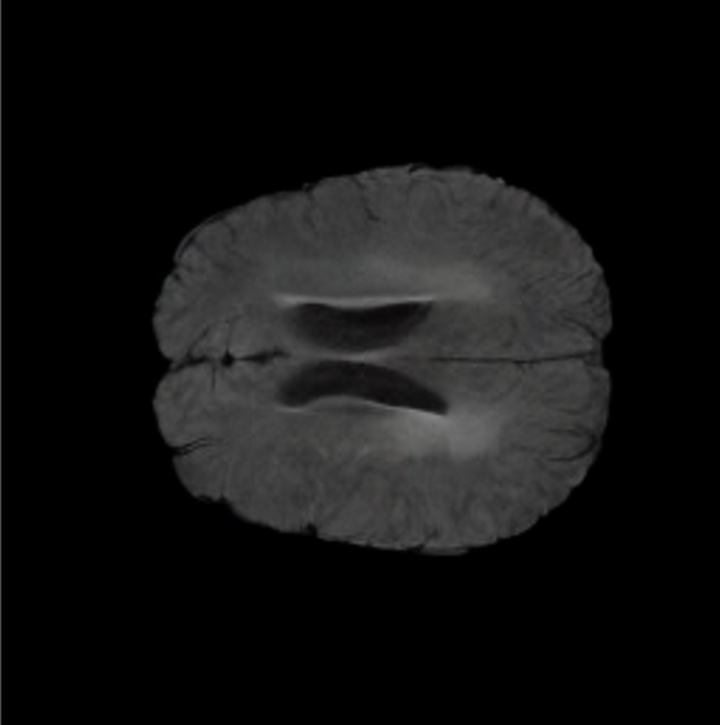

To see when and how X-Diffusion fails, we conducted an experiment on healthy brains (no tumour) using IXI dataset, by running an X-diffusion trained on BRATS brain tumor dataset. Our X-Diffusion achieved a PSNR of 35.86 dB on the IXI dataset despite being trained on the BRATS dataset. We then ran the tumour segmenter on the set of 582 healthy scans and corresponding generated MRIs. The segmenter predicted tumours in 9.9% of the real healthy brains and in 11.3% of the generated brain MRIs. Some of these tumor hallucination examples fron X-Diffusion generation are shown in Figure 10.

| Hallucination | Reference | Hallucination | Reference | Failure | Reference |